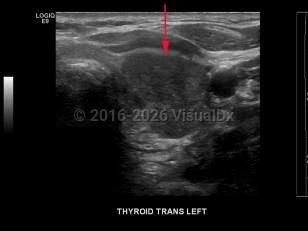

Signs and symptoms include a neck lump or swelling, neck pain, hoarseness, dysphagia, dyspnea, and/or persistent cough. Erythroderma may rarely be a cutaneous manifestation of malignancy.

Thyroid cancer is classified based on histologic features:

- Papillary thyroid cancer – The most common type of thyroid cancer (approximately 85% of cases), often with diagnosis at an early stage with good overall prognosis. Characteristic histologic findings include psammoma bodies, cleaved nuclei with an "Orphan Annie" appearance, and the formation of papillary structures. Of note, it is now suggested that the encapsulated follicular variant of papillary thyroid carcinoma, which has a very low risk of adverse outcome, be reclassified as noninvasive follicular thyroid neoplasm with papillary-like nuclear features.

- Follicular thyroid cancer – The most common type of thyroid cancer in iodine-deficient regions of the world. It is often difficult to diagnose with fine-needle aspiration due to a lack of distinguishing features. Prognosis is poor if diagnosis is made at an advanced stage of disease.

- Anaplastic thyroid cancer – A poorly differentiated and aggressive form of thyroid cancer. Most patients die within 6 months of diagnosis.

- Medullary thyroid cancer – This can either be sporadic or familial as part of multiple endocrine neoplasia type 2A (MEN2A), type 2B (MEN2B), or medullary thyroid cancer without other features of MEN. Surgical resection is the preferred method of treatment, with elevated calcitonin levels post-surgery indicating residual disease.